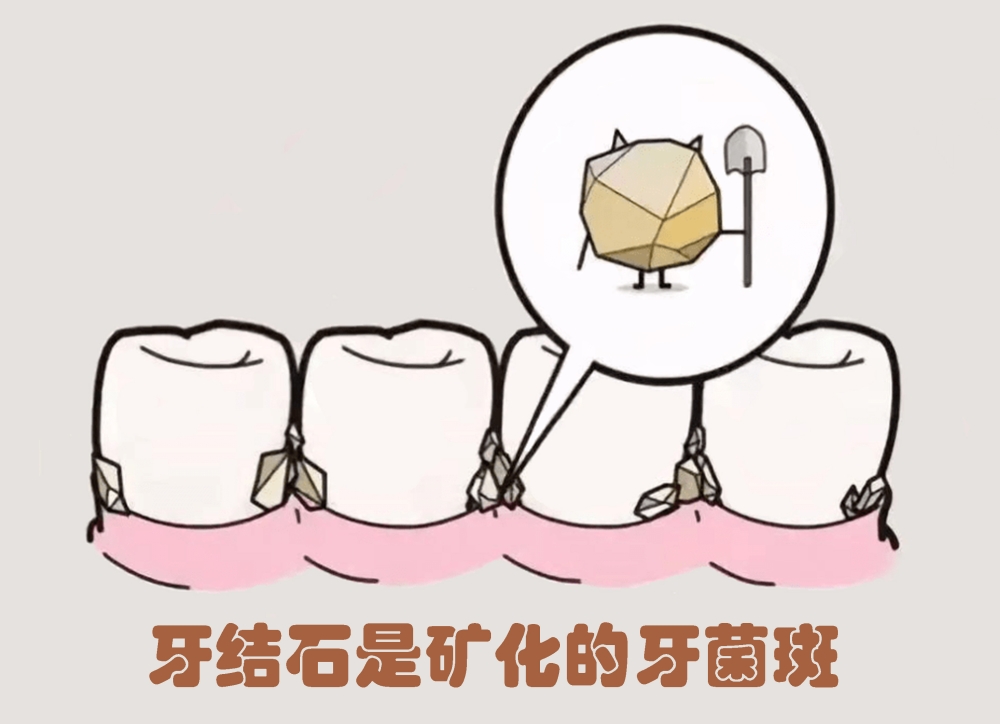

什么是牙结石 牙结石是指正在钙化或已经钙化的菌斑及软垢,沉积在

牙结石如何一步步"攻占"牙齿 牙结石由牙菌斑钙化沉积形成,是口腔健康

牙结石